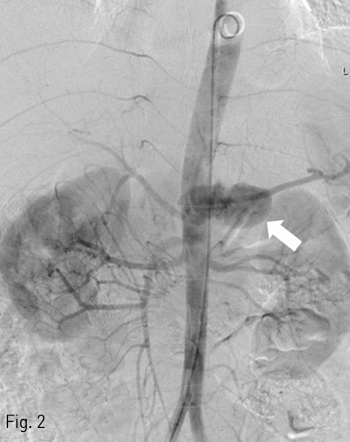

전산화단층촬영에서 자상으로 인해 대동맥에 거짓동맥류와 이와 관련한 광범위한 후복강 혈종이 보이고 있음 (Fig. 1A, B). 거짓동맥류가 생긴 위치는 복강동맥이 기시하는 높이의 뒤쪽 왼쪽인 5시 방향이었음. 이와 연관된 혈종은 후복강의 대동맥 주변과 횡격막 다리의 뒤쪽을 따라 연장되어 있었음. 그 외 다른 흉강이나 복강내 장기의 손상은 동반되지 않았음.

Fig 1A

Contrast-enhanced axial (A), coronal (B) CT scan demonstrates ruptured pseudoaneurysm (arrows) at posterior aspect of abdominal aorta causing redundant hemoretroperitoneum.